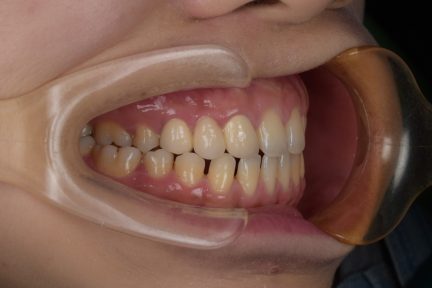

Classe I, morsure bord à bord, espacement, diastème

Facettes

Avec l'aimable autorisation du Dr F. Wang, 2021

État initial